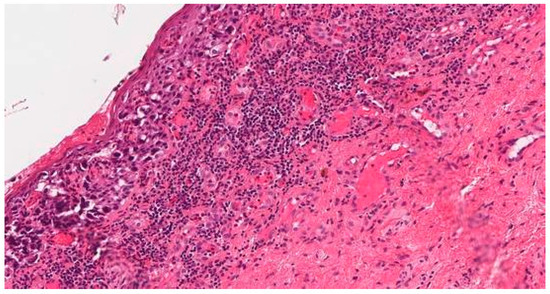

2. Case Report